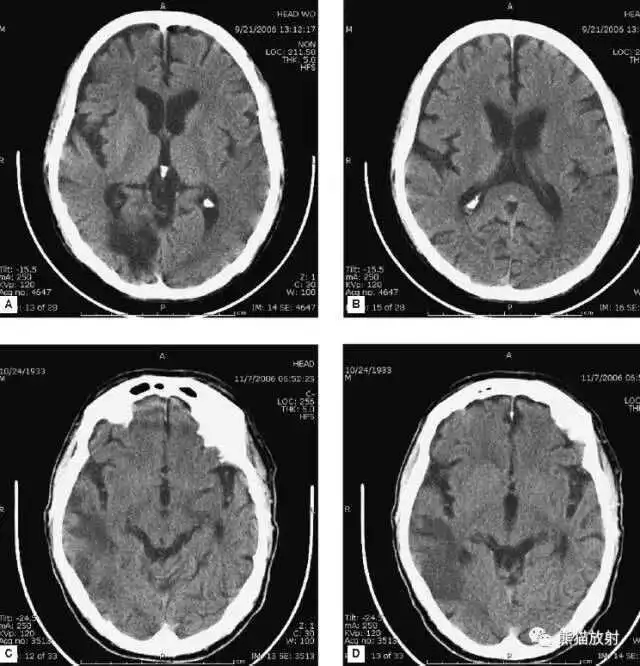

高血压性脑出血:

- 自发性出血;

- 继发于长期高血压及慢性血管病;

- 常见于基底节区、丘脑、脑桥、小脑。

A:占位效应,相邻脑沟、脑池消失;

F:脑出血破入四脑室。

▲

钩回疝:

是当代偿机制不能适应占位性病变时的结果。

基底节区大量高血压性脑出血,破入脑室及蛛网膜下腔,周围水肿,脑干周围空间消失;脑干出血、脑积水。